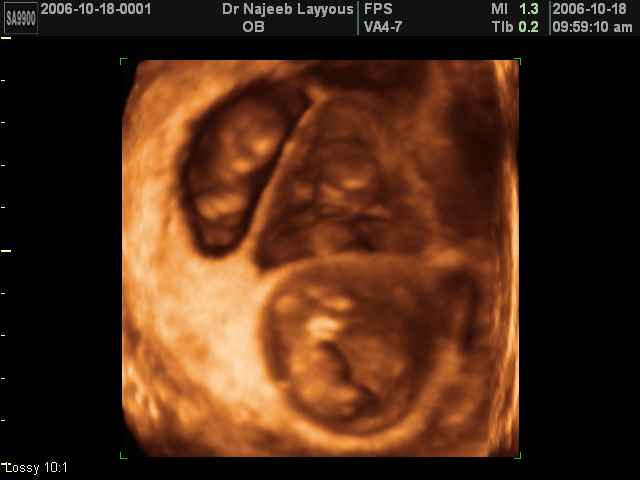

- صور لتوائم

صور لتوائم بجهاز الالتراساوند ثلاثي الأبعاد | الدكتور نجيب ليوس